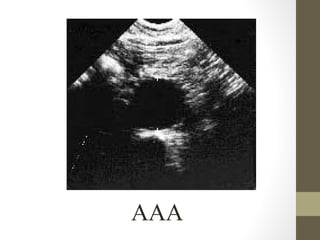

Radiography: Ultrasound

• Excellent for biliary tract disease (90+% sensitive for

gallstones)

• AAA- can rapidly assess size at bedside

• Ectopic pregnancy- look for intrauterine yolk sac, assess

adnexa, assess for free fluid

• Appendicitis- 75%-90% sensitive (in experienced hands, best

in thin patients)

• Pelvic structures, testicles

• Can also assess intussusception, obstructive kidney stone

Gallstones

AAA

• 62.

Rapid Case #4 •65 yo male • Hx of HTN, Renal Colic x3 episodes • Low back pain- ?new pain • Abd: obese, soft, no masses palpated • U/S shows 7cm AAA